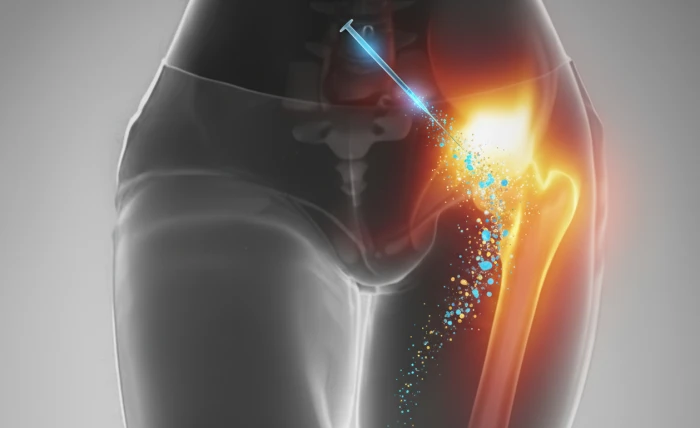

Procedimentos guiados e terapias regenerativas com células sinalizadoras que tratam a causa da dor e estimulam a recuperação dos tecidos.